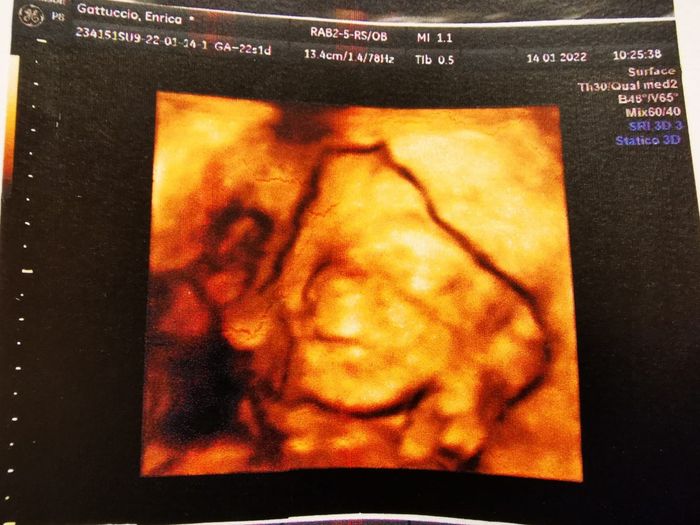

Da Enrica , Il 14 Gennaio 2022 alle 13:20

Ciao ragazze! Ho visto che noi mamme di maggio siamo mooolto coraggiose ehπ€£π€£ quindi.. anche se probabilmente sono la meno indicata, con tanta gioia apro io il gruppo!...